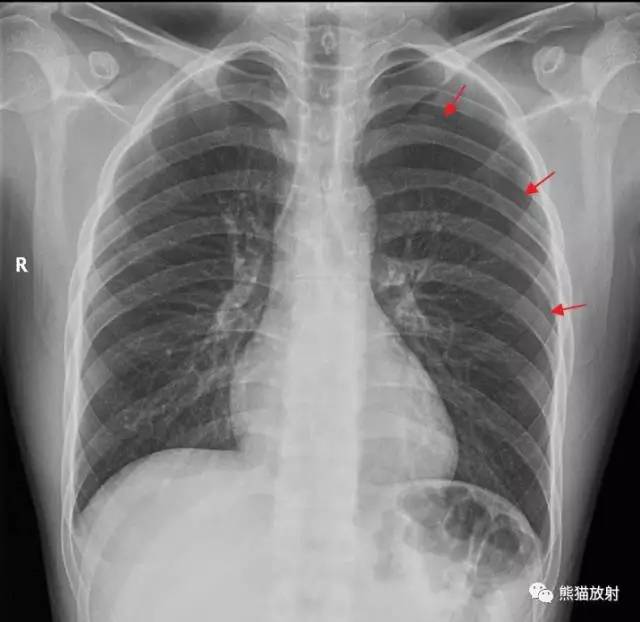

气胸x线胸片典型表现

典型气胸x线胸片图解

气胸x线胸片图解

气胸的x线表现

气胸x线胸片表现

气胸x线胸片描述

气胸x线胸片

气胸X线

气胸胸片